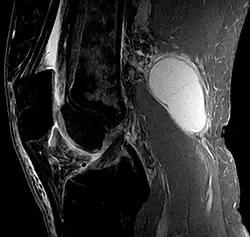

Baker's cyst on MRI, sagittal image Baker's cyst on MRI, sagittal image